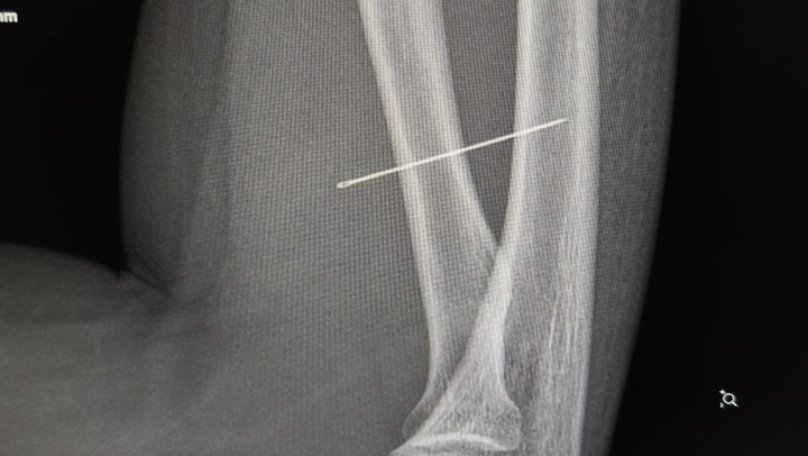

Під час огляду лікарі запідозрили сторонній предмет і направили дитину на УЗД м’яких тканин, де й виявили голку. Згодом рентген підтвердив, що вона зайшла під кутом 45 градусів і застрягла глибоко в товщі м’яза, продовжуючи мігрувати всередині тіла.

Під час операції лікарям було критично важливо витягнути голку точно за траєкторією її входження, аби вона не зламалася. За допомогою рентген-навігації ЕОП хірурги точно визначили місце стороннього тіла, виконали невеликий розріз і безпечно його видалили.